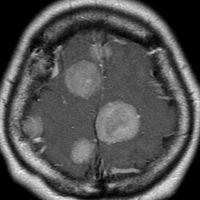

多発例,NF-2ではないもの

30代で下肢の局所てんかん発作で発見されました。テント上硬膜の腫瘍化です。数えれば総数で30個以上はあったでしょう。このタイプは手術で硬膜を広範囲切除(ほとんど全頭蓋冠)することで治すことができます。